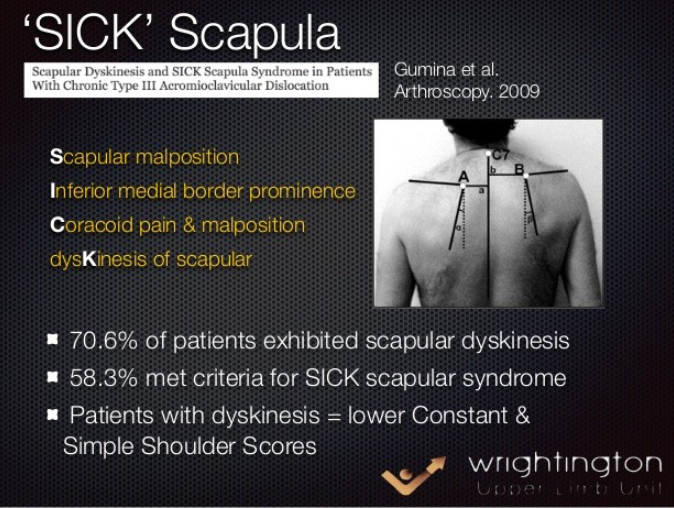

▶ SICK scapular syndrome

견갑골 운동장애 시 흔히 동반되는 이상소견들을 모아 증후군으로 표현한것으로서 어깨를 많이쓰는 운동선수에서는 SLAP이나 Dead arm syndrome이 나타나기전 증상일 수 있습니다.

Scapular malposition

Inferior medial border prominence

Coracoid pain & malposition

Dyskinesis of scapular